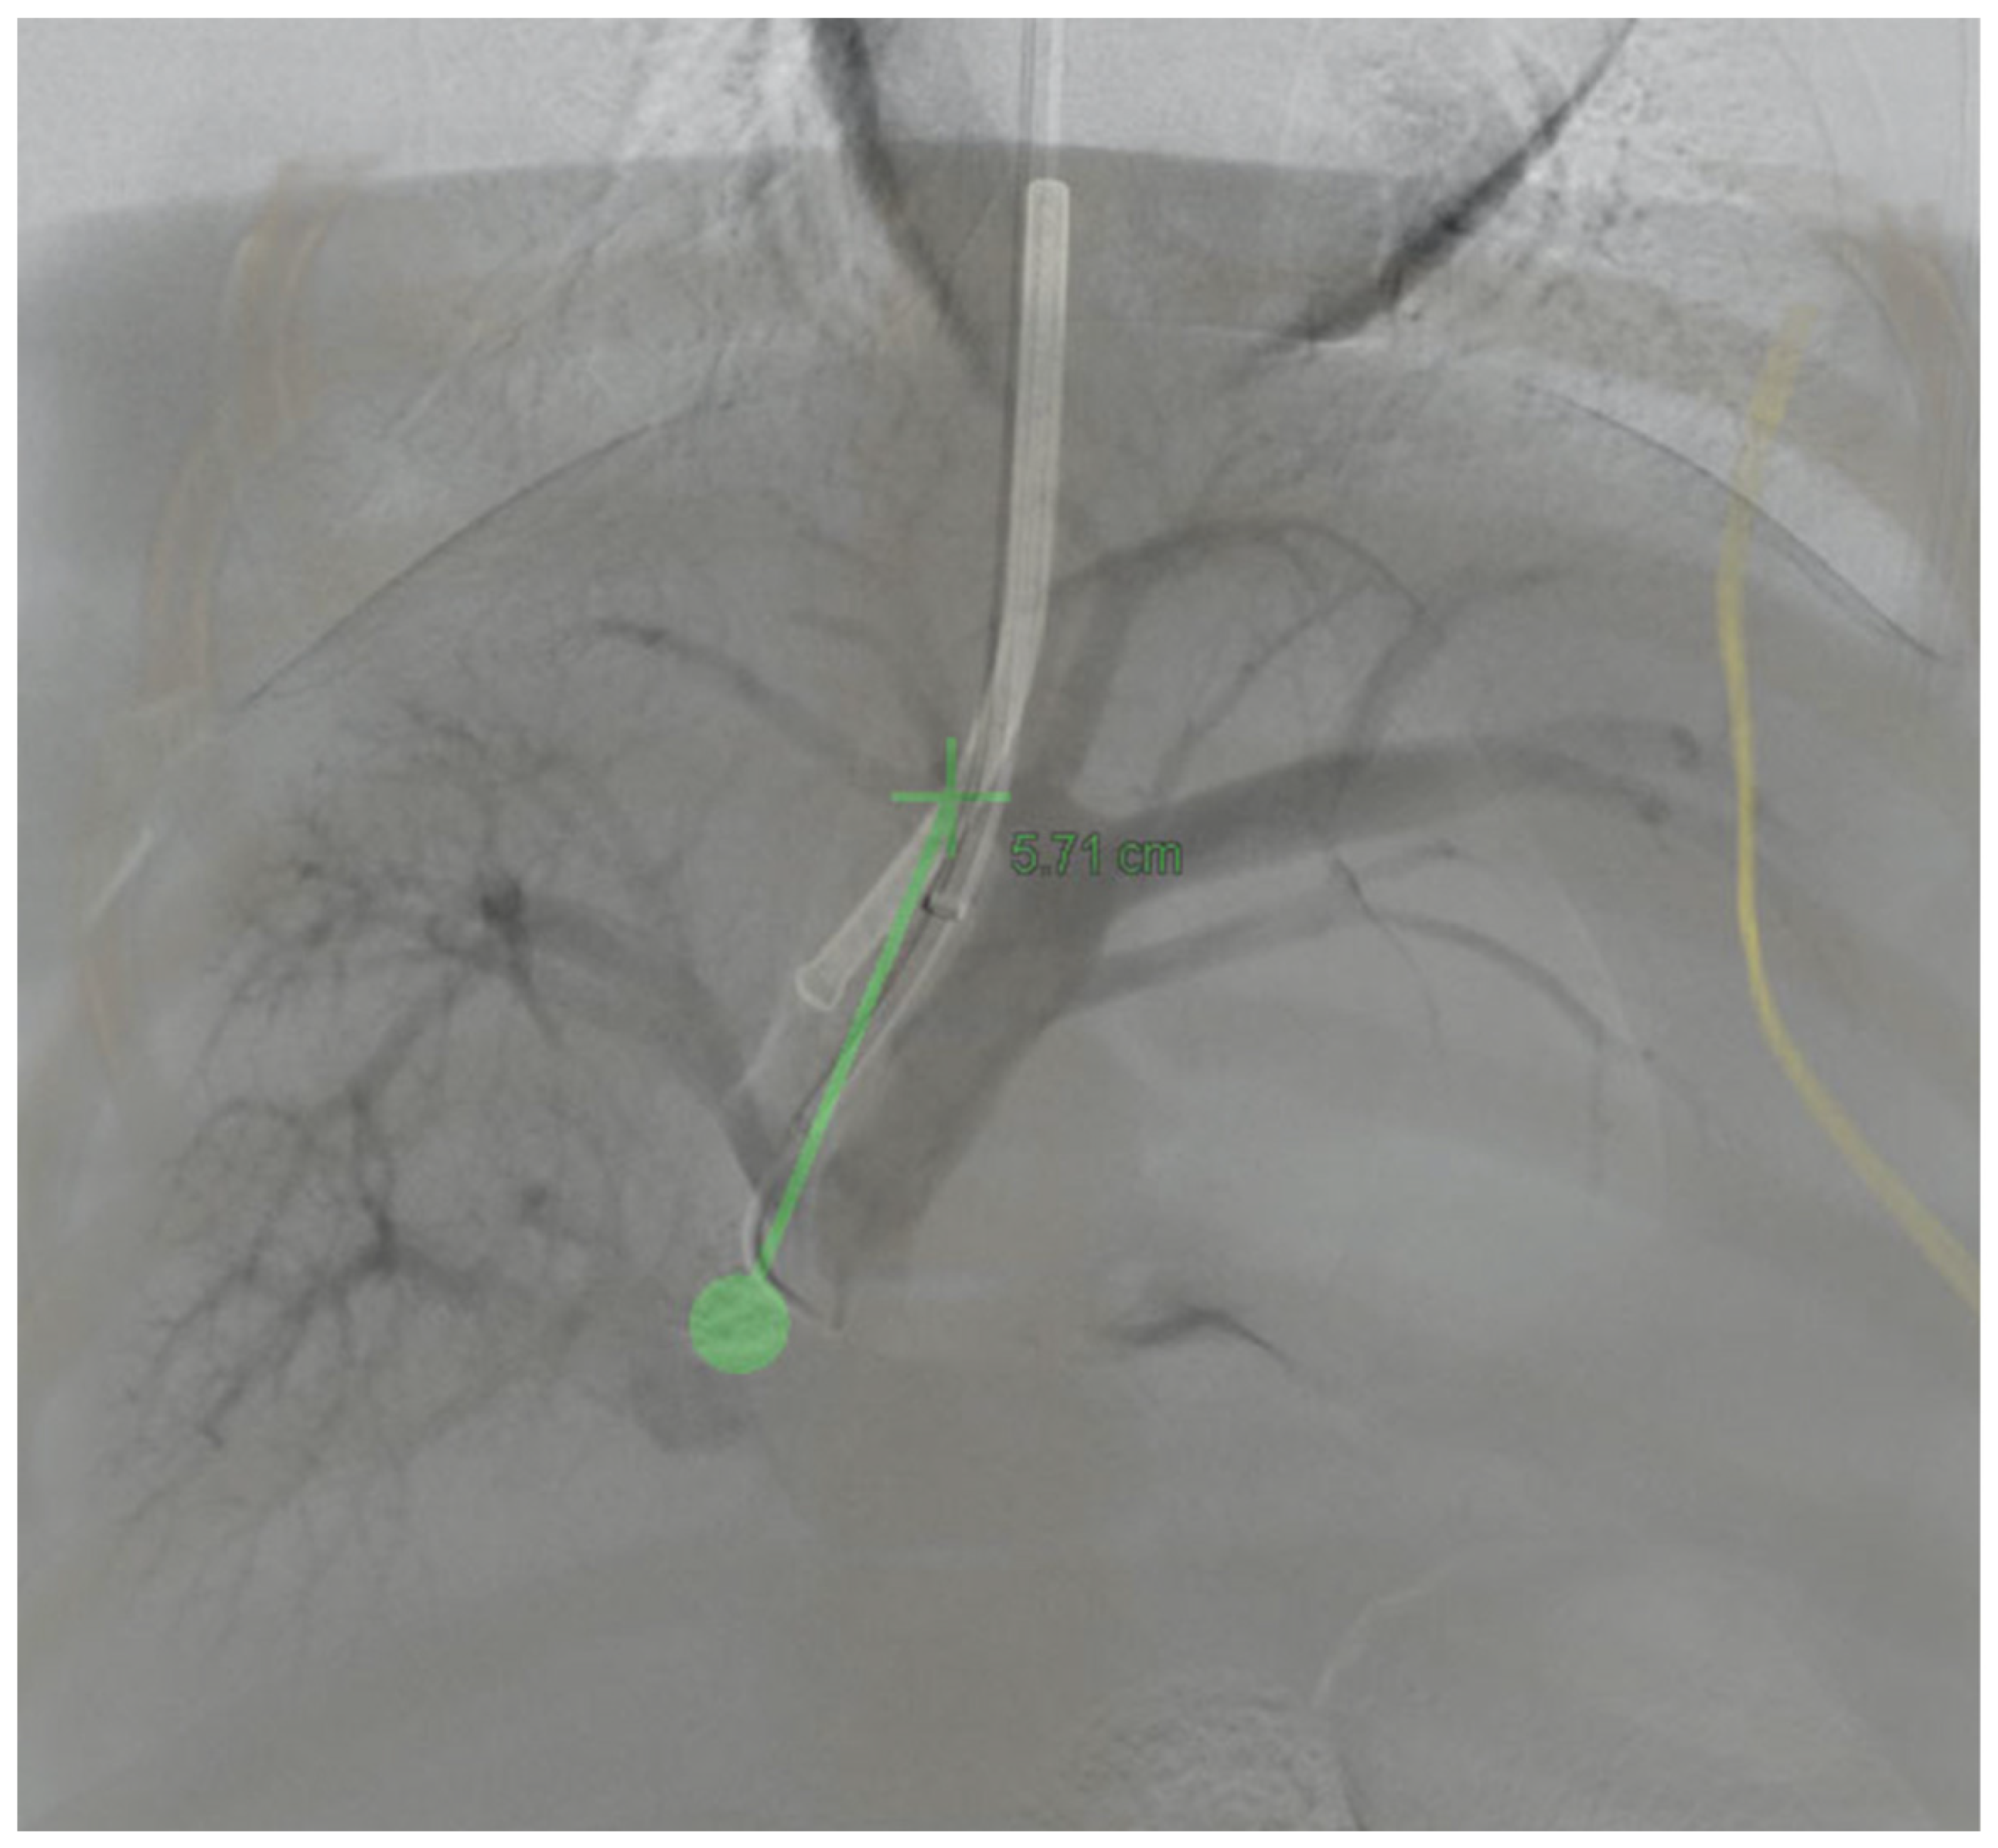

2.5. TIPS and DIPS Creation Using 3D Image Guidance

3.3. 3D Angiography-Guided TIPS Using CBCT/Angiography-Fused Images

3.4. 3D Angiography-Guided DIPS Using CT/CBCT/Angiography-Fused Images